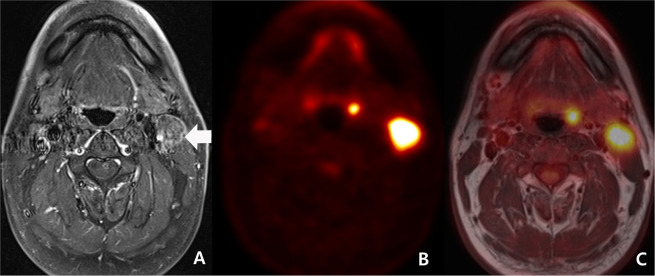

In discordant cases, PET/MRI had a sensitivity of 71.4%, a specificity of 81.3%, a PPV of 62.5%, a NPV of 86.7%, and an accuracy of 78.3%. (Fig. 2)

Figure 2.

Initial work-up of a 54-year-old man with left palatine tonsillar cancer (discordant diagnosis) and ipsilateral cervical lymph node metastasis (malignant concordant diagnosis). (A) A transverse fat-suppression contrast enhanced MRI revealed enhancing lesion at left cervical chain (arrow). A neuroradiologist scored the lesion as 5 (definitely malignant). However, he failed to reveal primary focus in the scan. (B) As PET reveals hypermetabolism (maximal SUV: 12.3) at the left cervical chain, a nuclear medicine specialist scored the lesion as 5 (definitely malignant). In addition, because PET shows a small hypermetabolic lesion at left palatine tonsil (maximal SUV: 8.3), he scored the lesion as 4 (probably malignant). (C) A consensus score of PET/MRI for left cervical lesion was 5 (definitely malignant) and a consensus score of the left palatine tonsillar lesion was 4 (probably malignant). Both left cervical chain lesion and left palatine tonsillar lesion were proved to be squamous cell carcinoma.

Independently in these discordant cases, PET had a sensitivity of 42.9%, a specificity of 50.0%, a PPV of 27.3%, a NPV of 66.7%, and an accuracy of 47.8%. MRI had a sensitivity of 57.1%, a specificity of 50.0%, a PPV of 33.3%, a NPV of 72.7%, and an accuracy of 52.2%. The 11 discordant cases with malignant diagnosis on PET and benign diagnosis on MRI comprised 9 non-nodal lesions and 2 nodal lesions. Among them, MRI was correct in 6 out of 9 non-nodal lesions and 2 out of 2 nodal lesions. The 12 discordant cases with benign diagnosis on PET and malignant diagnosis on MRI comprised 4 non-nodal lesions and 8 nodal lesions. Among them, PET was correct in 8 out of 8 nodal lesions and MRI was correct in 4 out of 4 non-nodal lesions.

While NPV was not statistically different between benign concordant cases (84.6%, 44/52) and discordant cases (86.7%, 13/15), PPV was larger in malignant concordant cases (93.2%, 55/59) than in discordant cases (62.5%, 5/8) (p = 0.0404) (Figs. 1, 2).